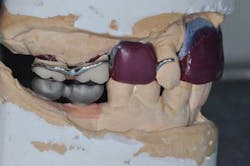

Figs. 6 a, b, c, and d: RPD framework try-in, bite record with mandibular implant-supported metal frameworks and mounting

- Final mounting.

Figs. 7a, b, and c: Teeth and ceramic mounting